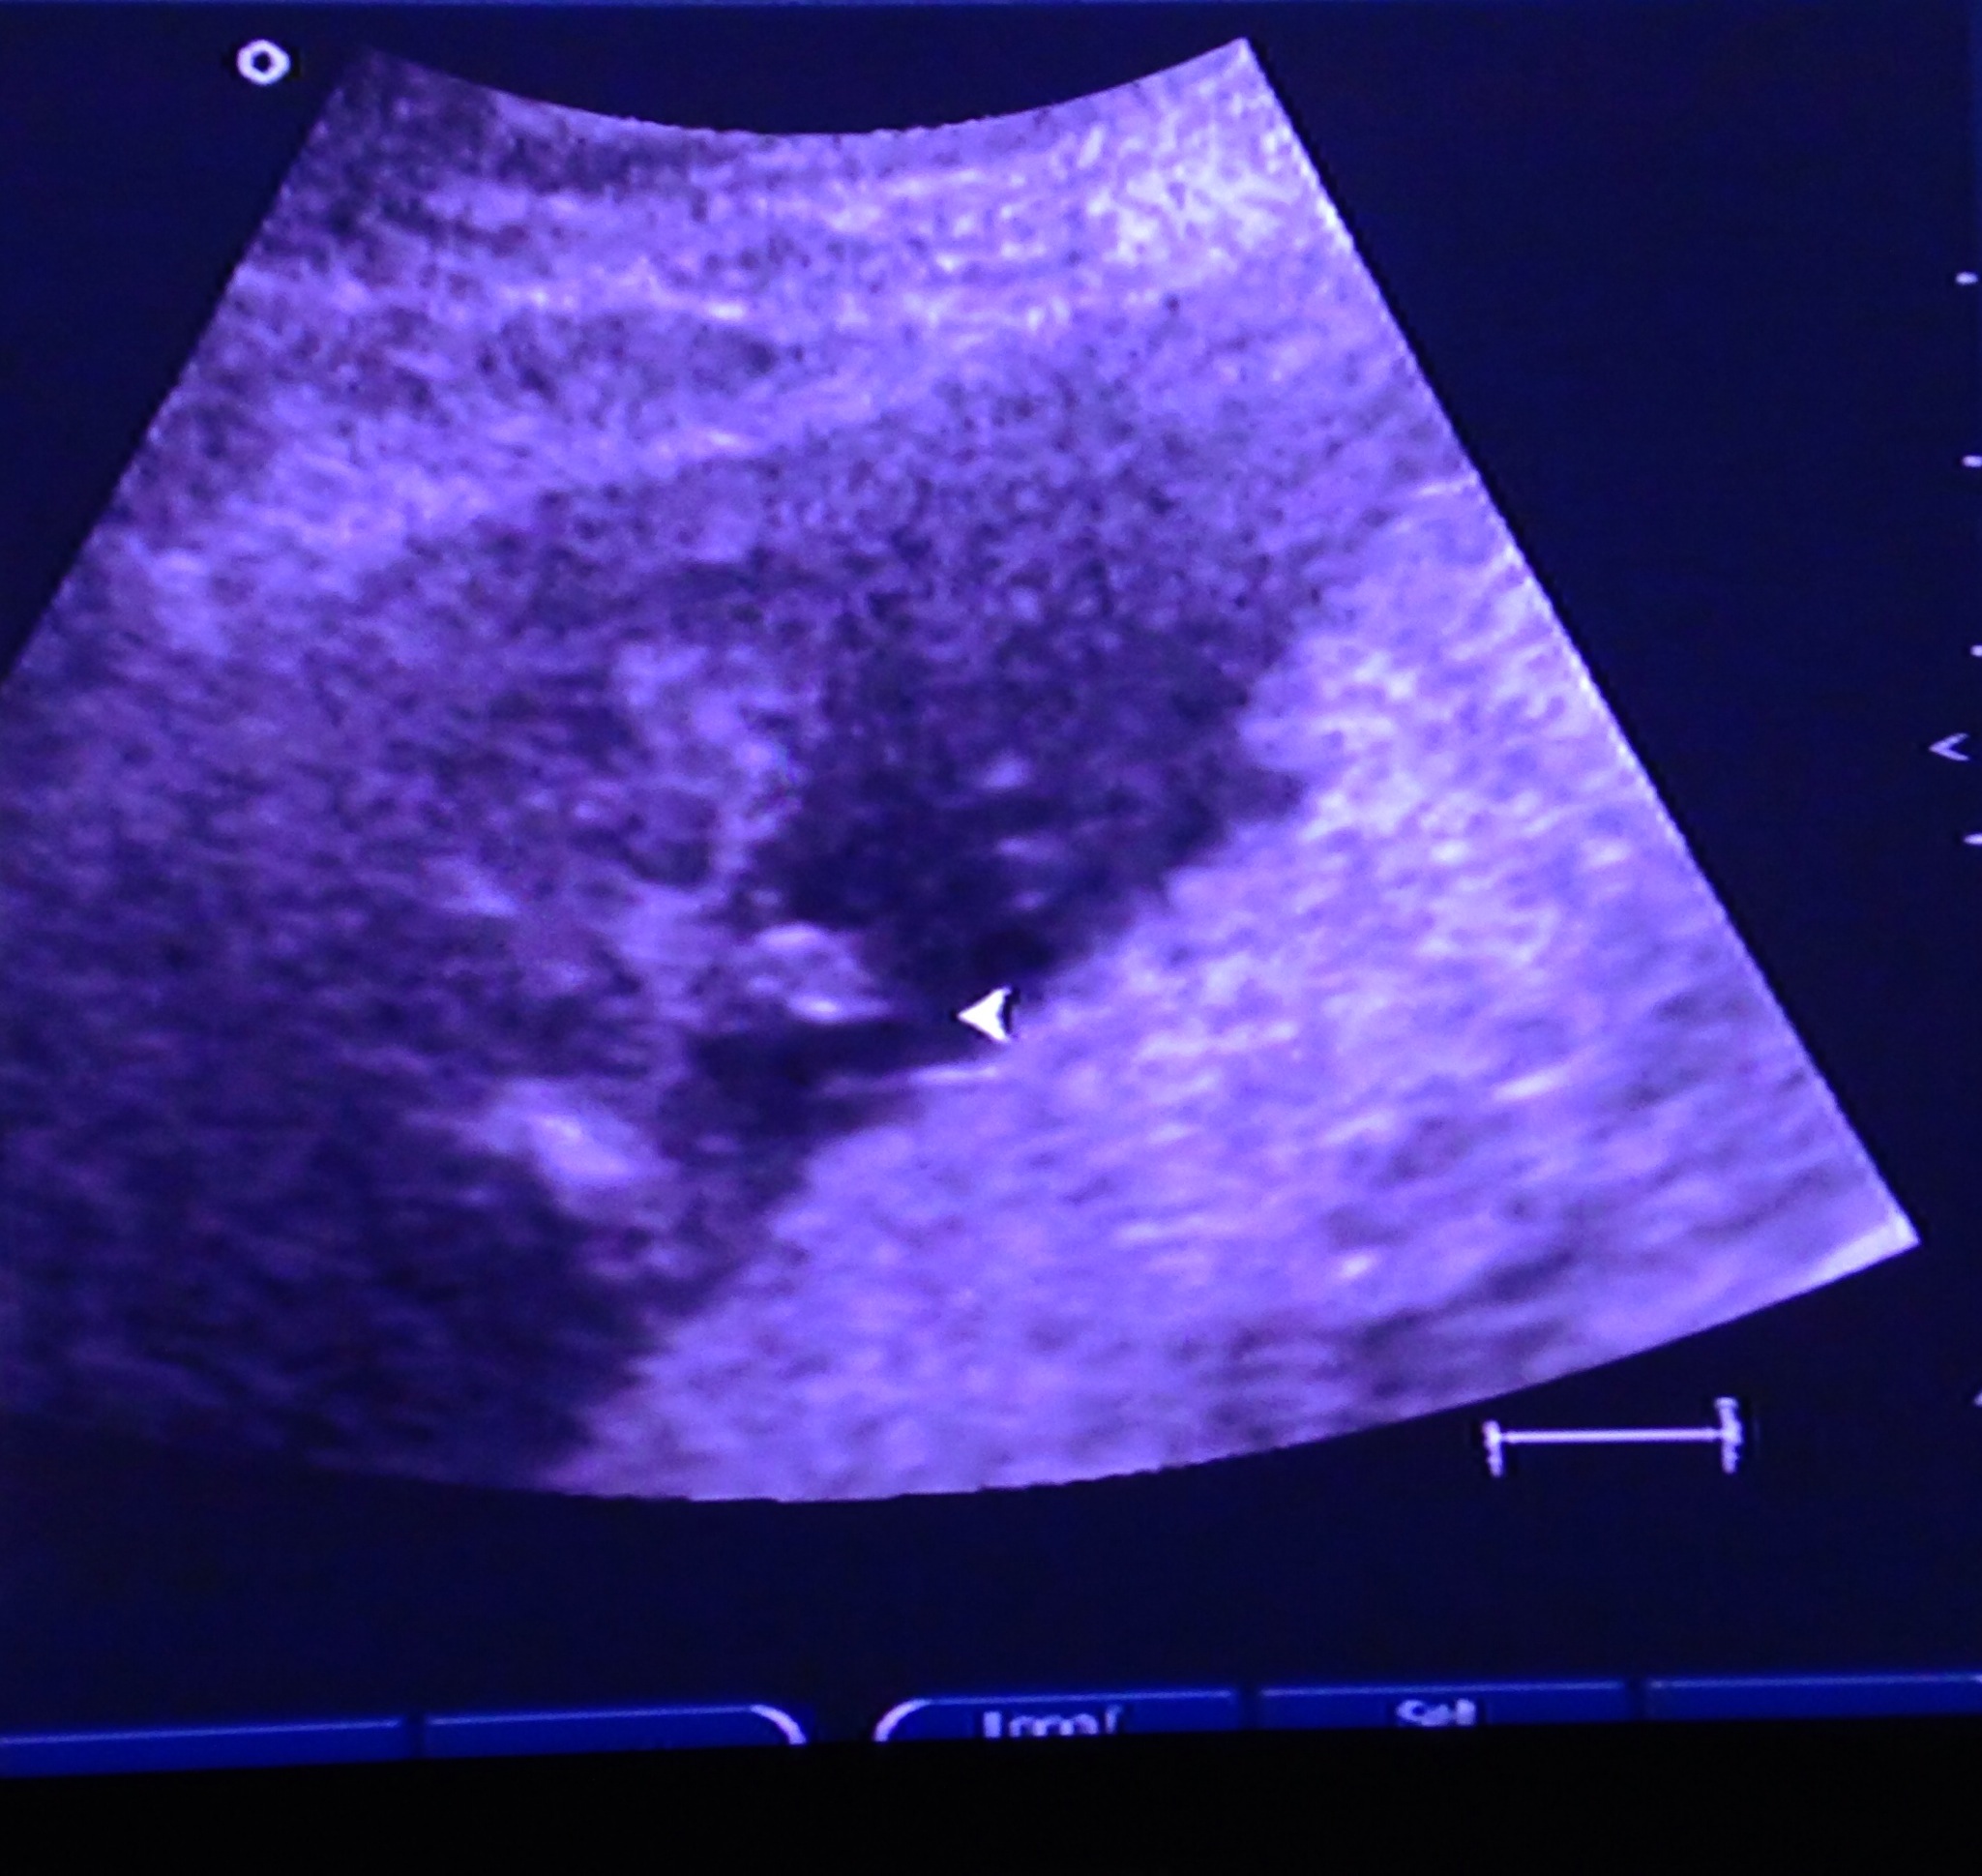

Is this a def boy?? I have 3 boys already, and I was so sure this baby was a girl. Totally different pregnancy than my other three.